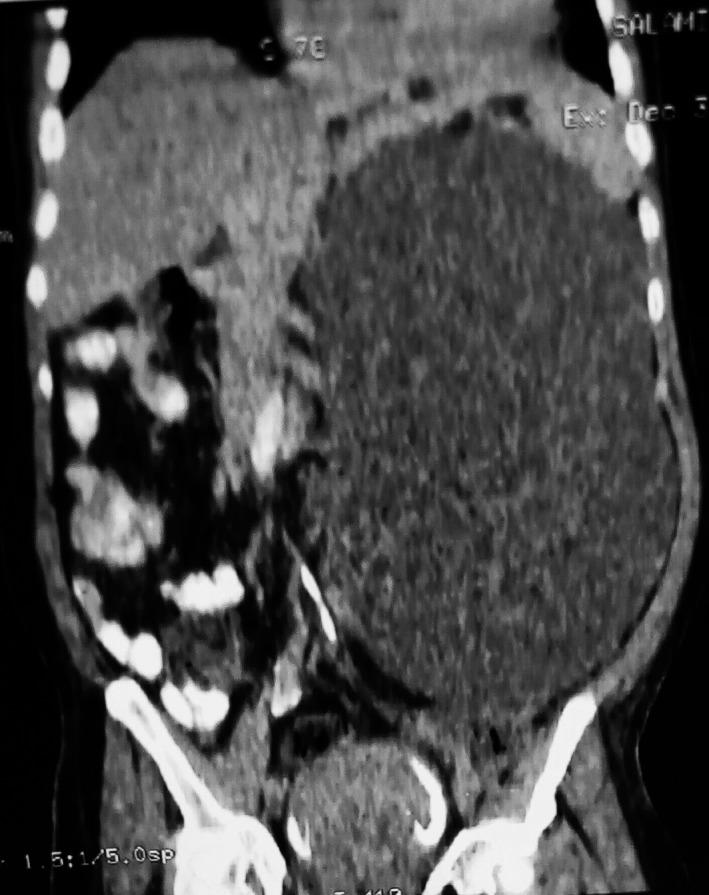

Giant Adrenal cysts are rare differentials of retroperitoneal cysts that often present dilemma in diagnosis. A man presented with a huge retroperitoneal cyst and an uncertain preoperative diagnosis. Initial working diagnosis of urinoma and an attempt at drainage had to be abandoned for complete excision before obtaining a histological diagnosis.

巨大肾上腺囊肿是腹膜后囊肿的罕见鉴别诊断,常给诊断带来难题。一名男性患者出现巨大腹膜后囊肿,术前诊断不明确。最初初步诊断为尿囊肿,并尝试进行引流,但在获得组织学诊断之前,为了完整切除囊肿,不得不放弃引流。